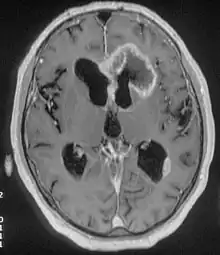

There are many different causes of frontal lobe epilepsy ranging from genetics to head trauma that result in lesions in the frontal lobes.[4] Although frontal lobe epilepsy is often misdiagnosed, tests such as prolonged EEG monitoring, video EEG and/or an MRI scan of the frontal lobes can be administered in order to reveal the presence of a tumor or vascular malformation.[4] Unlike most epileptic EEGs, the abnormalities in FLE EEGs precede the physical onset of the seizure and aid in localization of the seizure's origin.[4] Medications such as anti-epileptic drugs can typically control the onset of seizures, however, if medications are ineffective the patient may undergo surgery to have focal areas of the frontal lobe removed.[4]